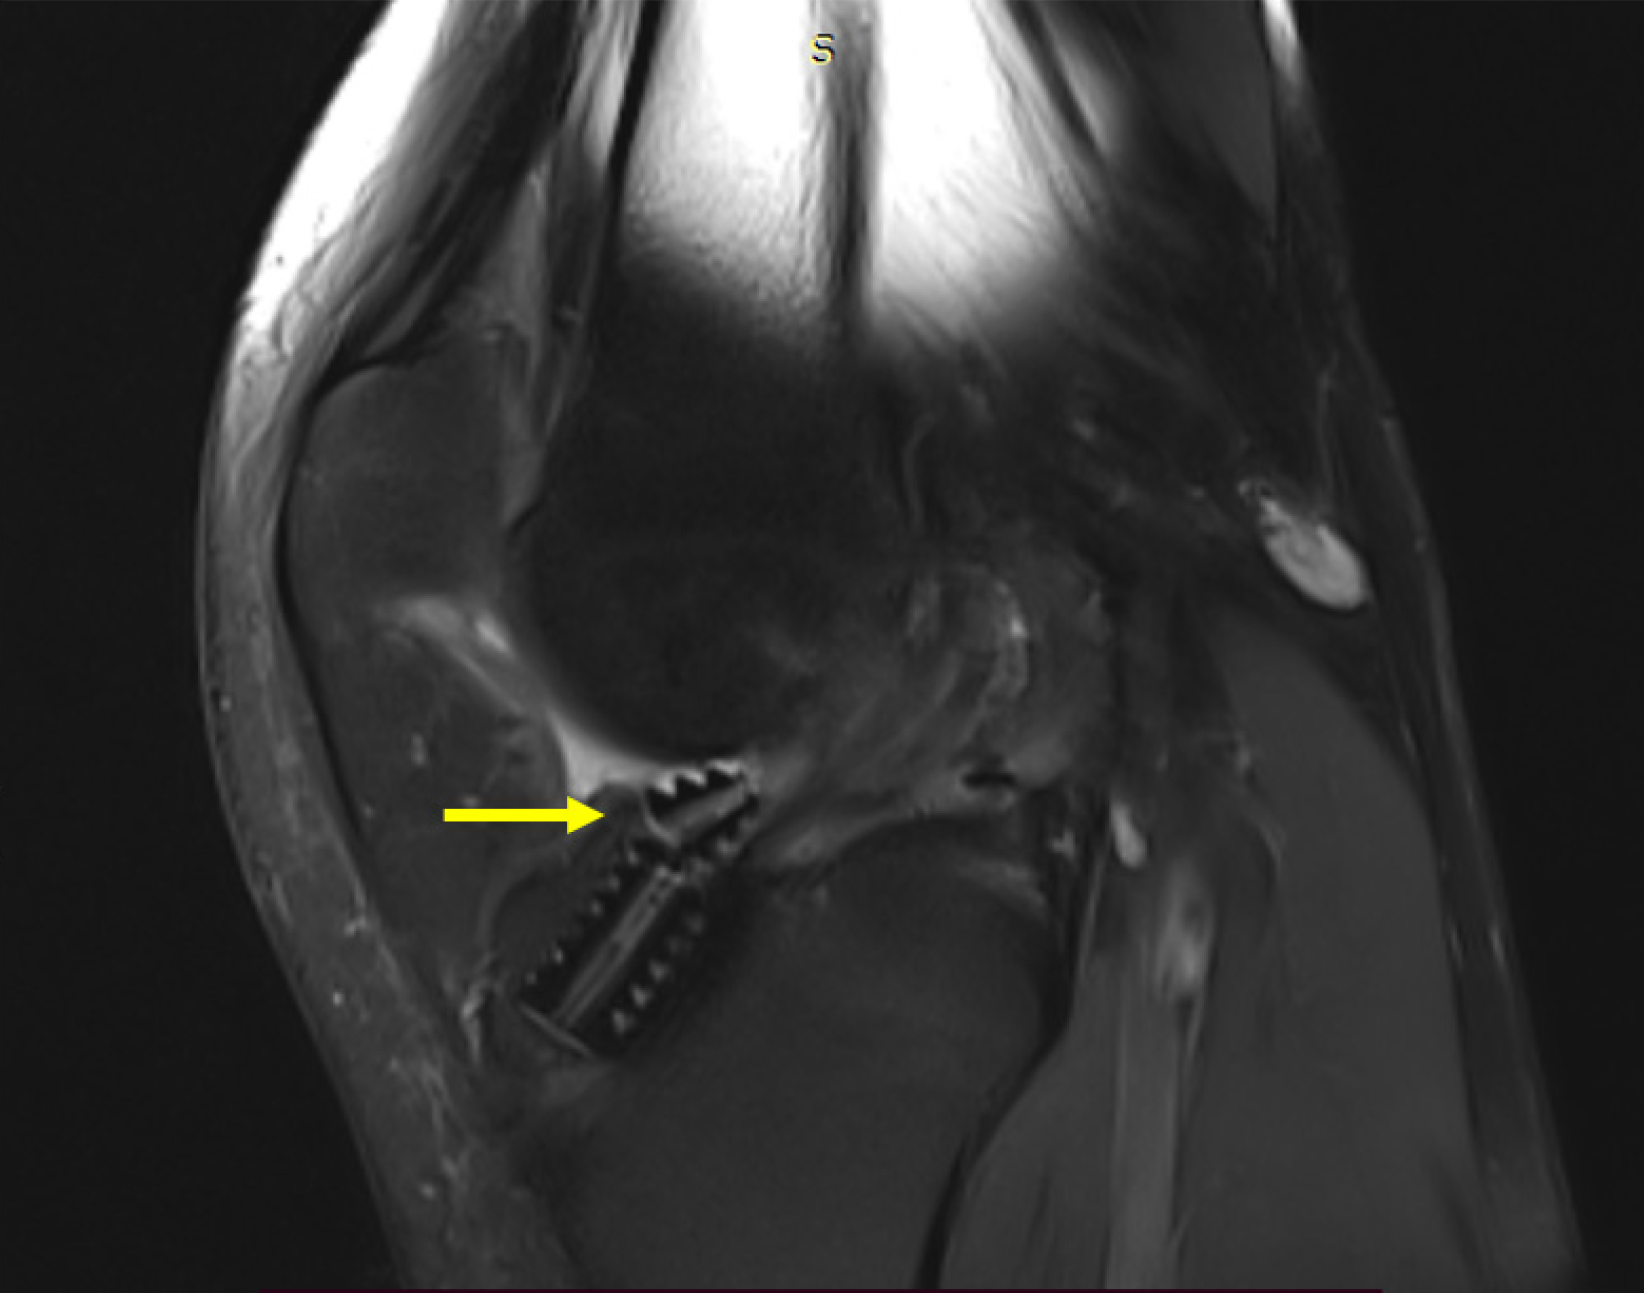

Figure 2

Magnetic resonance imaging images of coronal and sagittal section showing intra-articular migration of broken bioabsorbable tibial screw.